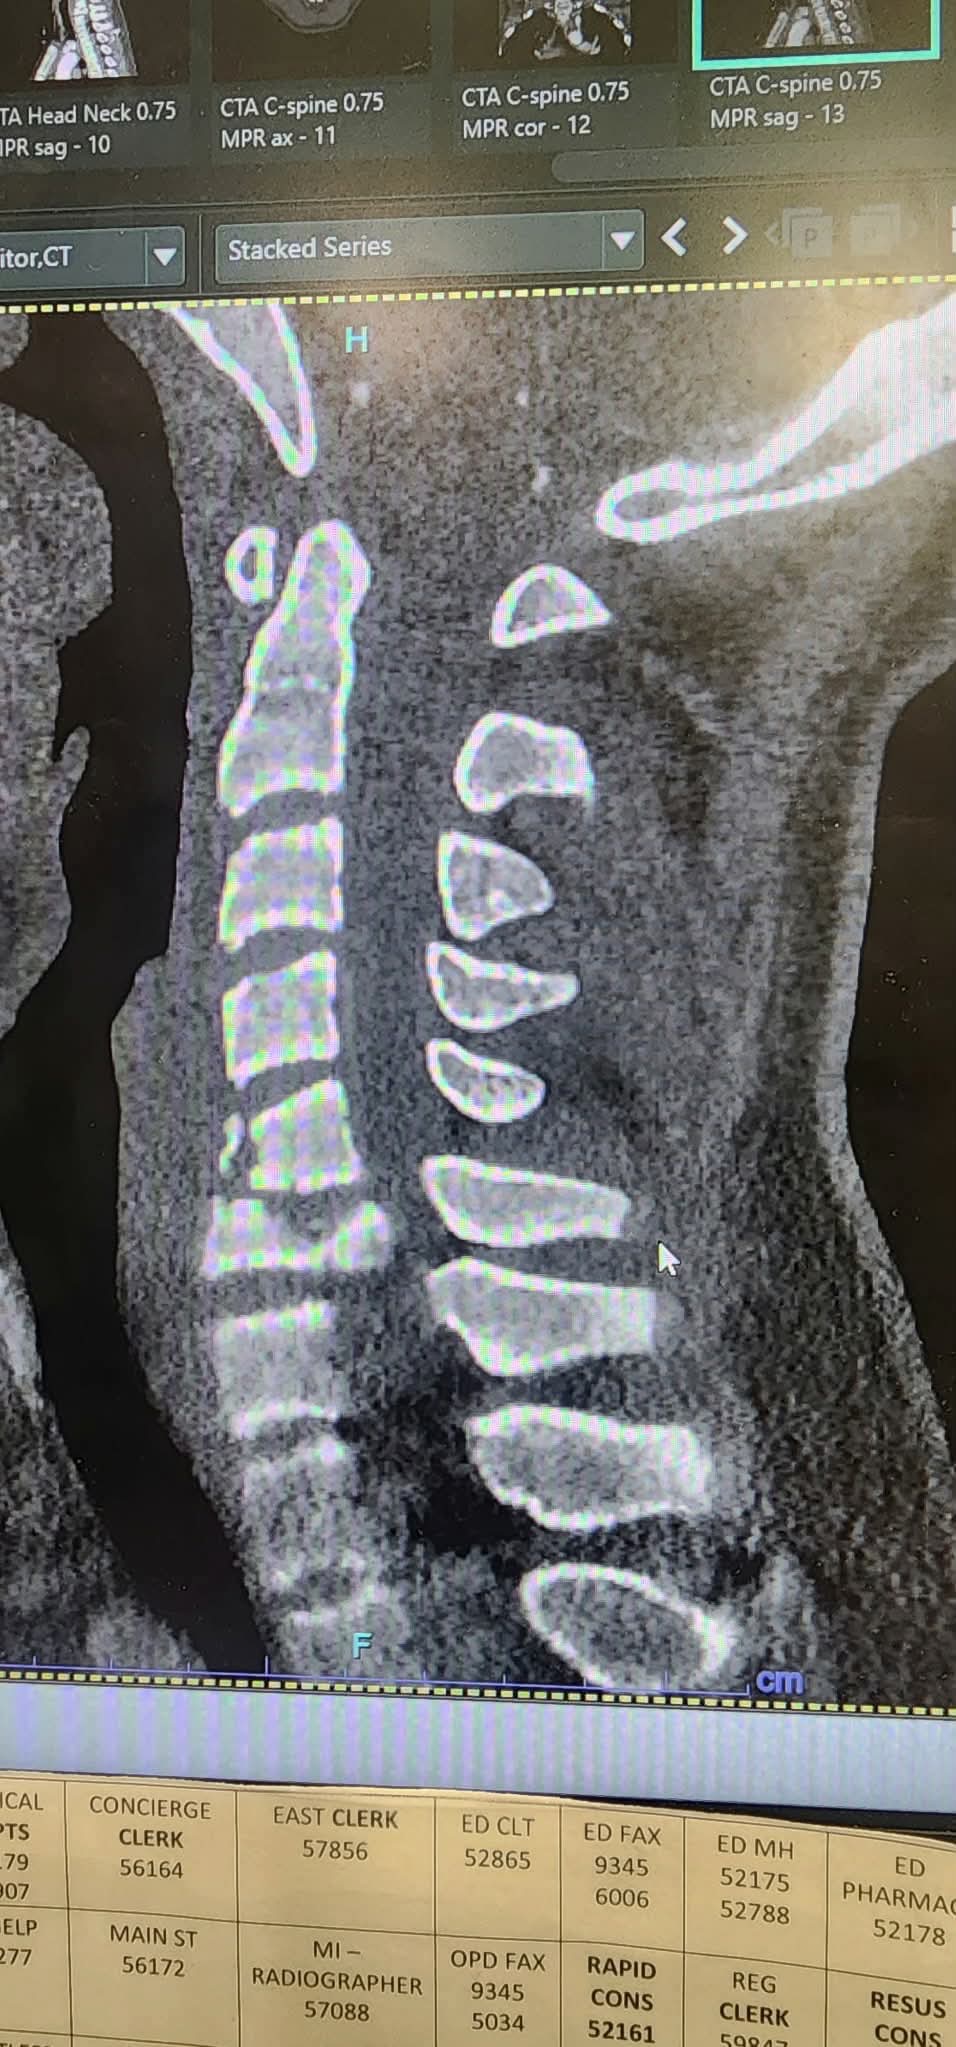

On Saturday the 31st of January my nephew Kaiden went to his friends birthday party. He was having fun with his friends jumping through a hoop into the pool when unfortunately he landed on his head breaking his neck in 2 places and his lower back he immediately lost mobility in his body. He was rushed to the Royal Children’s hospital where he went straight in for surgery to put a metal plate in his neck to release the pressure off of his spinal cord. He is currently still in ICU with no mobility to his body they are unsure if he will ever gain it back.